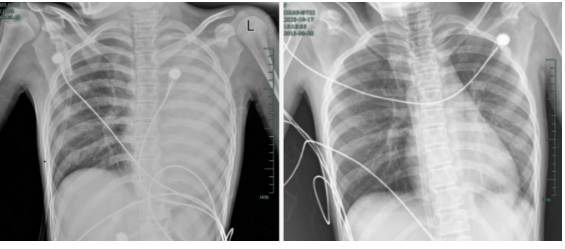

治疗前后影响对比,左肺从“白肺”到正常状态。

呼吸急促、胸闷胸痛,体温38.5℃,只能靠 5L/min 的面罩吸氧维持血氧,胸片显示左肺已完全呈 “白肺” 改变,肺部炎症进展迅猛。